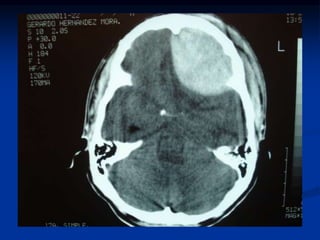

Hematoma Subdural

La TAC muestra la imagen hiperdensa

biconcava en la superficie.

HEMATOMA EPIDURAL

caso clinico

 Historia de Mexico

 En los pueblos pequeños

hay fiestas, alcohol y

traumas

 Joven que salio a la fiesta

tomo alcohol, se peleo

,llego a su casa en la

madrugada , atáxico

 Se quedo dormido todo

el domingo

 Se opero de manera

inmediata por el Dr.

Salvador Rodriguez

Peralta